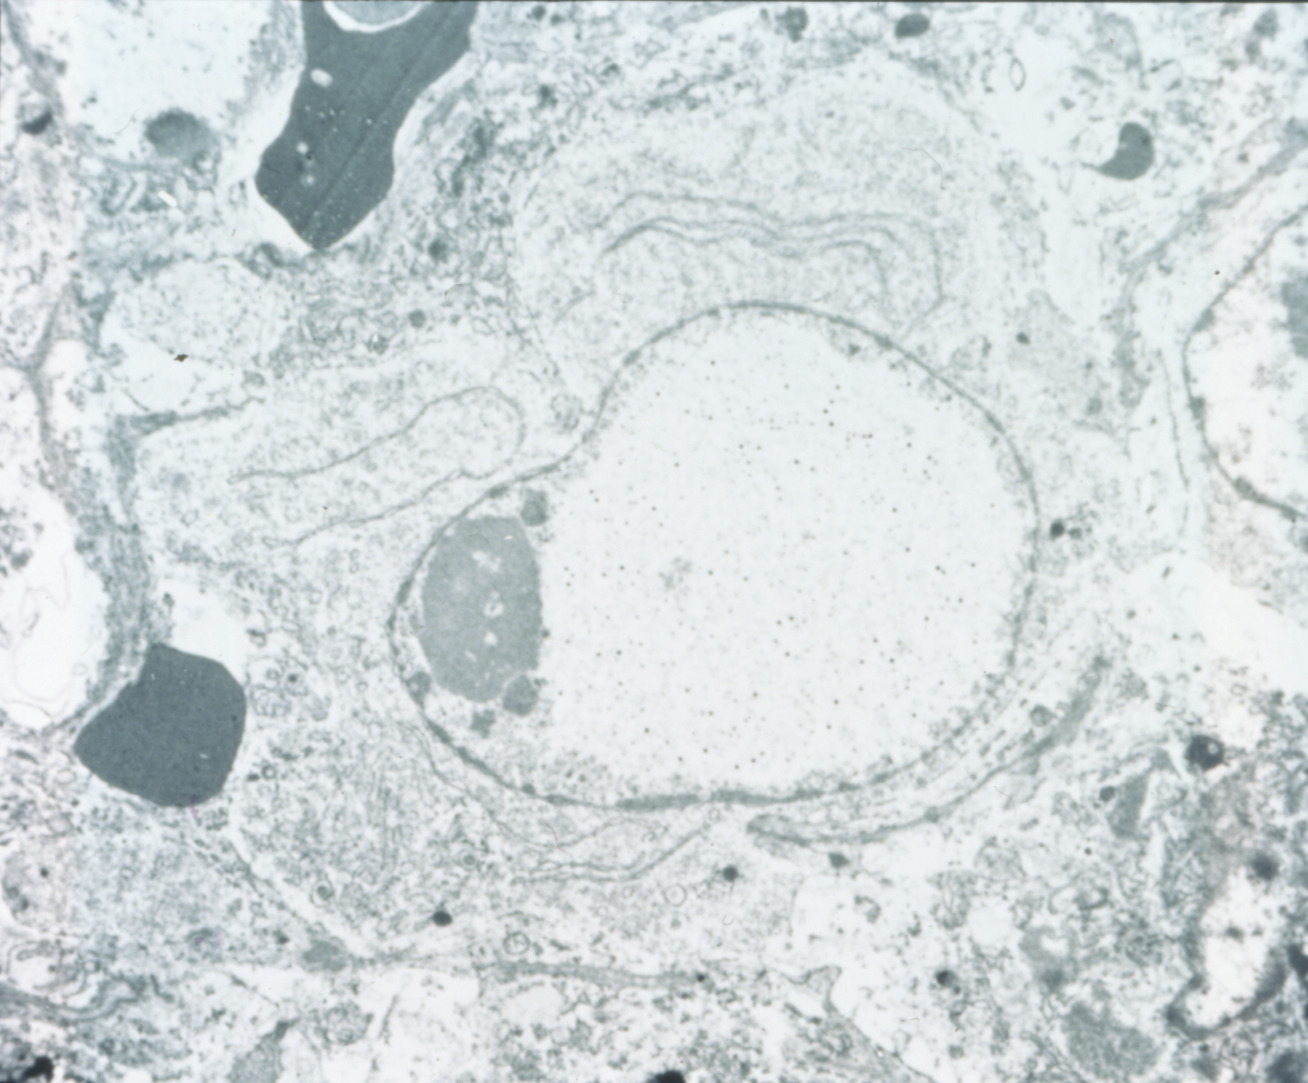

Marble spleen disease of ring-necked pheasants (slide study set no. 17) Item Info

Marble spleen disease of ring-necked pheasants (slide study set no. 17)

Poultry--Diseases Spleen--Diseases Ring-necked pheasant

Slide Study Set #17, Marble Spleen Disease of Ring-Necked Pheasants (includes 20 color slides), 1992